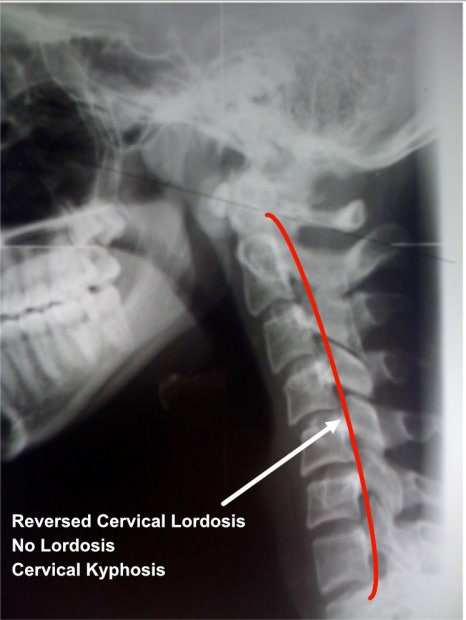

일자목(거북목): 정상적인 C자형 목뼈가 수직으로 변형된 상태입니다. 주로 잘못된 자세로 인해 근육과 인대에 과도한 긴장이 쌓여 발생합니다.

1️⃣ X-ray 검사: 목뼈의 정렬 상태와 일자목/거북목의 진행 정도를 파악합니다.